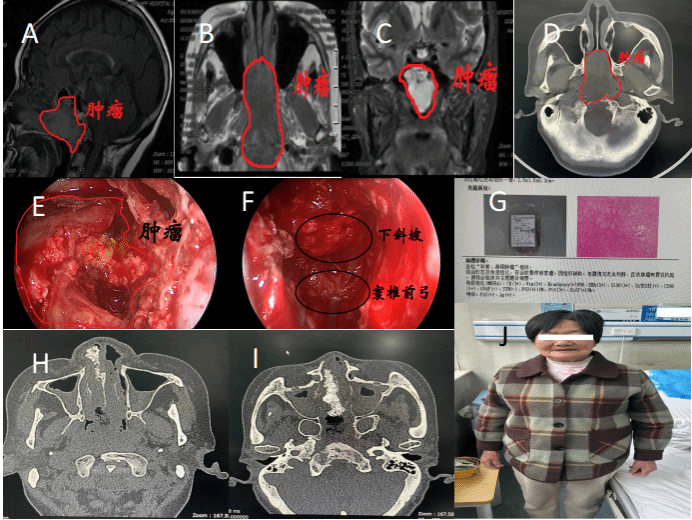

入院相关检查发现,肿瘤巨大,主体位于颅底,侵袭并破坏斜坡和蝶窦骨质,寰椎前弓等部骨质已悉数破坏,两侧紧邻基底动脉及双侧颈内动脉斜坡旁段,向后毗邻脑干;肿瘤前界已突入中鼻道和下鼻道,下界已突入口咽顶部。随着肿瘤的生长侵袭,有可能进一步向脑干及口咽方向侵袭,最终造成患者窒息、严重的神经功能障碍,甚至死亡。

图 A-D术前肿瘤影像结果;E内镜下切除蝶窦腔内肿瘤情况;F内镜下肿瘤切除后探查寰椎前弓及下斜坡等结构;G术后病理;H-I术后复查鼻窦CT;J患者术后恢复情况

为提高手术的成功率,降低术中风险,神经外科刘重霄教授团队在术前为患者制定了详尽的个体化手术方案。术中通过神经内镜角度调整,充分显露下斜坡段,尤其是脑干腹侧骨质侵袭破坏最为明显的环枢椎部;利用好肿瘤的假包膜标识,防止对颈内动脉斜坡旁段的损伤;尽可能保留带蒂的鼻中隔-鼻底粘膜瓣,减少可能致命的下斜坡段脑脊液漏;应用神经导航,在脑干腹侧部再次精准定位,防止对脑干的损伤;同时应用等离子刀在肿瘤非核心区切除,控制术中出血。手术当天,雷晓明教授、刘鸿涛主治医师负责全身麻醉,师蔚教授和周任教授现场指导,刘重霄教授主刀,郭振宇副主任医师和黄廷钦博士配合,在神经内镜下“抽丝剥茧”,顺利切除肿瘤。术中出血控制良好,约400ml;脑干腹侧硬膜未见明显脑脊液漏。患者术后恢复良好,未再诉头疼,于术后10天出院。